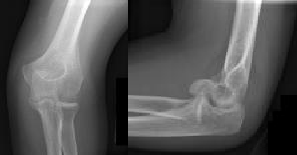

Figures 1 and 2 are the radiographs of a 35-year-old man who has elbow pain after falling from a ladder onto an outstretched hand. Examination reveals elbow pain, swelling, limited motion, and normal neurologic function.